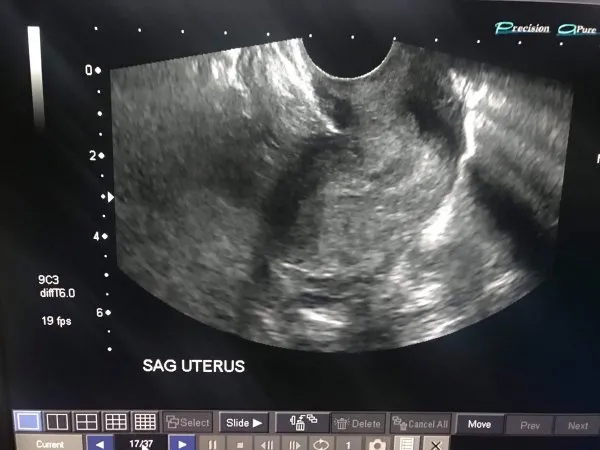

¿Estoy embarazada de mi ultrasonido? ¿Qué es un útero del sag? gracias de antemano

- Kravmama1 op inactivo, Sag útero describe cómo toman la foto. Esta es una descripción para que el radiólogo esté orientado a lo que mira. Dicho esto, es una imagen de la visión del útero. Y esta es toda esta imagen específica. Estoy seguro de que tienes otros que te dirán más si estás embarazada o no.

SAG significa Sagital, que es la guía de la sonda. No tiene absolutamente nada que ver con algo más allá de describir el ángulo que suponen en la imagen.

La imagen suministrada no muestra un embarazo positivo o negativo.

Debe hablar con su médico si desea saber los resultados de su ultrasonido.